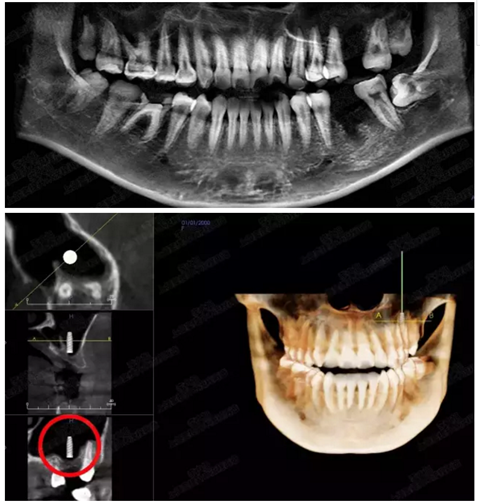

病例二

剩余骨量2mm

003.png

提升10mm

004.png

病例三

剩余骨量3mm

005.png

006.png